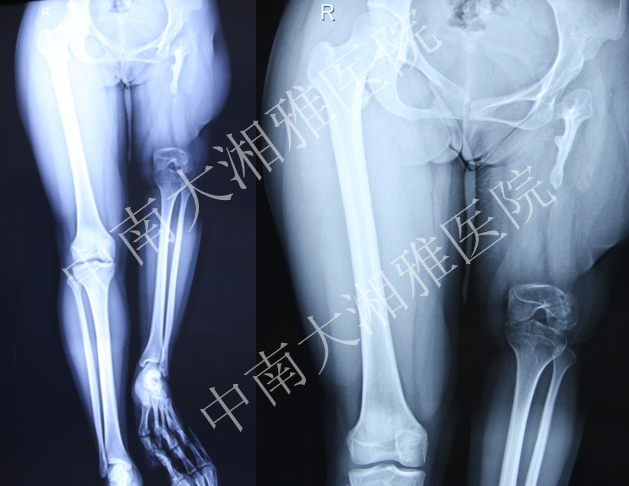

中南大学湘雅医院—全股骨置换病例讨论

患者,女,21岁。

主诉:左下肢短缩,活动不能21年

出生后8个月出现左股骨中段骨髓炎,在当地医院予以保守治疗,1年后好转。其后出现左大腿停止发育,左下肢短缩,行走活动不能。2012年10月至中南大学湘雅医院门诊求治,摄片发现左股骨未发育,收入住院。

入院诊断:左股骨骨髓炎后遗股骨发育不良

2013年4月软组织延长术后

2013年5月髋臼置换

2013年6月安装胫骨侧假体,自制股骨骨水泥占位器占位,继续延长

2013年10月复查双下肢长度恢复

Final Game—2013年10月

术后2月复查—2013年12月